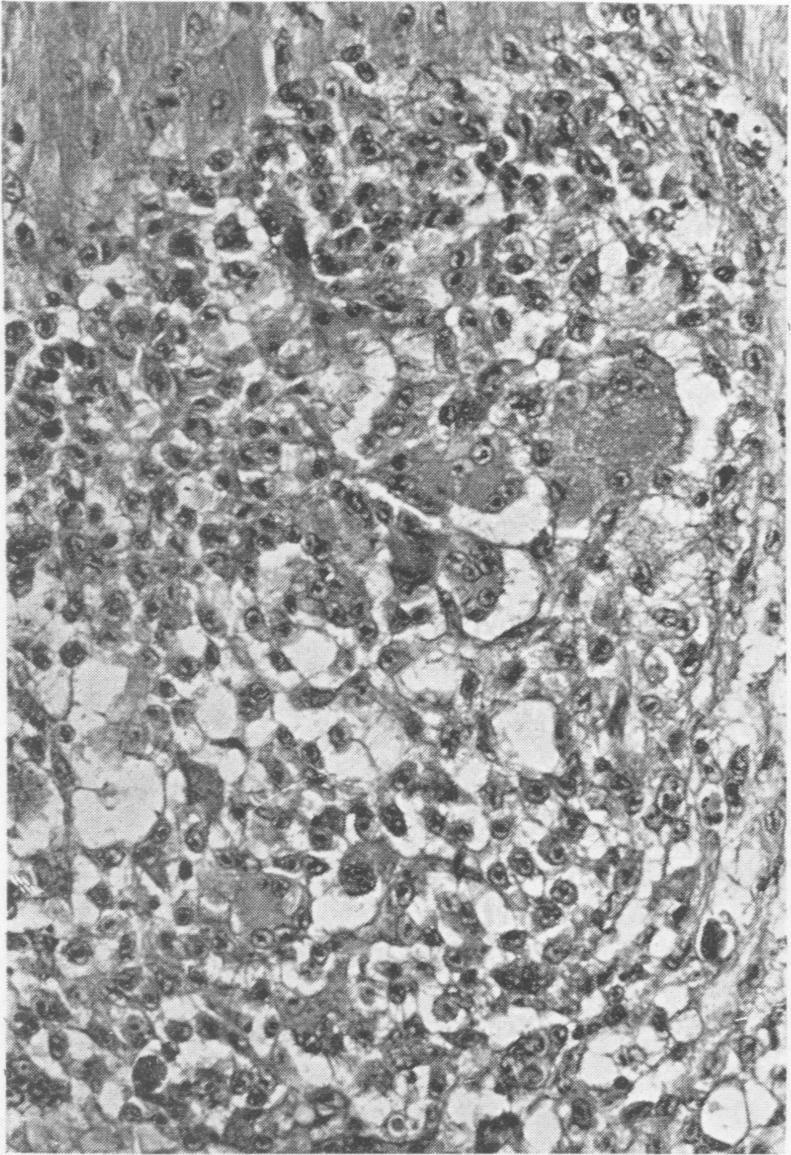

Rations containing 25% of either regular rapeseed oil (36% erucic acid), Oro rapeseed oil (1.9% erucic acid), soybean oil or a mixture of lard and corn oil were fed to chickens, ducks and turkeys. The regular rapeseed oil ration caused growth depression, increased feed conversion and anemia in all species. All the ducks and some of the chickens fed the regular rapeseed oil ration died. These dead birds were affected with hydropericardium and ascites. No deaths in the turkeys could be attributed to the regular rapeseed oil ration but some turkeys fed this ration had degenerative foci characterized by infiltrations of histiocytic and giant cells in the myocardium. Severe fatty change in the heart, skeletal muscles, spleen and kidney was found at an early age in all birds fed the regular rapeseed oil ration. Less severe fatty change but no other lesions were found in birds fed the Oro rapeseed oil and soybean oil rations.

将含有25%普通菜籽油(芥酸含量36%)、奥罗菜籽油(芥酸含量1.9%)、大豆油或猪油与玉米油混合物的日粮喂给鸡、鸭和火鸡。普通菜籽油日粮导致所有品种的生长抑制、饲料转化率提高和贫血。所有喂食普通菜籽油日粮的鸭子以及部分鸡死亡。这些死亡的禽类患有心包积水和腹水。火鸡的死亡不能归因于普通菜籽油日粮,但一些喂食该日粮的火鸡有以心肌组织细胞和巨细胞浸润为特征的退行性病灶。在所有喂食普通菜籽油日粮的禽类中,早期就发现心脏、骨骼肌、脾脏和肾脏有严重的脂肪变性。喂食奥罗菜籽油和大豆油日粮的禽类脂肪变性较轻,但未发现其他病变。